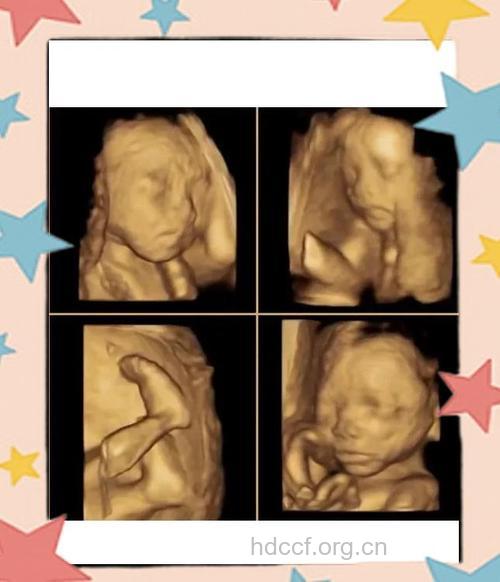

三维彩超和四维彩超的区别就在于在一个“时间维”,也就是说,三维彩超是图片,四维彩超是录像,可以让孕妈妈看到胎儿一连串的动作。四维彩超是动态的,三维彩超是静态的,所以四维看起来会更清楚明,三维彩超只能是某个时间点上的照片,四维彩超就可以做成DV那样连续的,可以刻录光盘。三维彩超和高清四维彩超一样的有排畸的作用,高清四维彩超更加精确。

四维彩超最佳的时间是在怀孕24~28周之间。在孕24周之前,你的宝宝皮肤下的脂肪还非常少,所以脸部的骨骼会透过皮肤突显出来。而孕28周以后,宝宝长大,有的宝宝的头可能会进入你的骨盆,这样你就会看不到他的脸了。